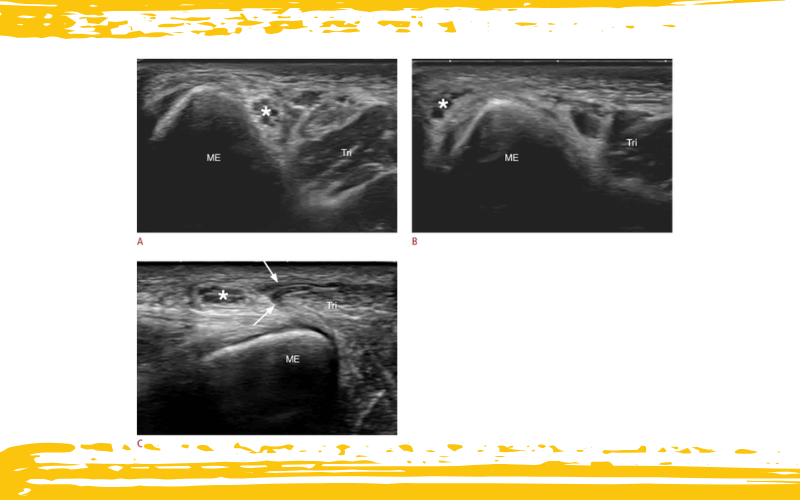

Imágenes ecográficas dinámicas de un varón de 22 años con síndrome de snapping triceps

A. La vista ecográfica en eje corto del codo posteromedial en extensión muestra el nervio cubital (asterisco) situado posterior al epicóndilo medial (ME).

B. La vista ecográfica en eje corto del codo en flexión demuestra la luxación del nervio cubital (asterisco) hacia anterior con respecto al ME.

C. La vista ecográfica en eje corto del codo en flexión máxima ilustra la subluxación del vientre medial del músculo tríceps (flechas) sobre el ME, empujando el nervio cubital (asterisco) hacia anterior.

Tri: tríceps braquial.